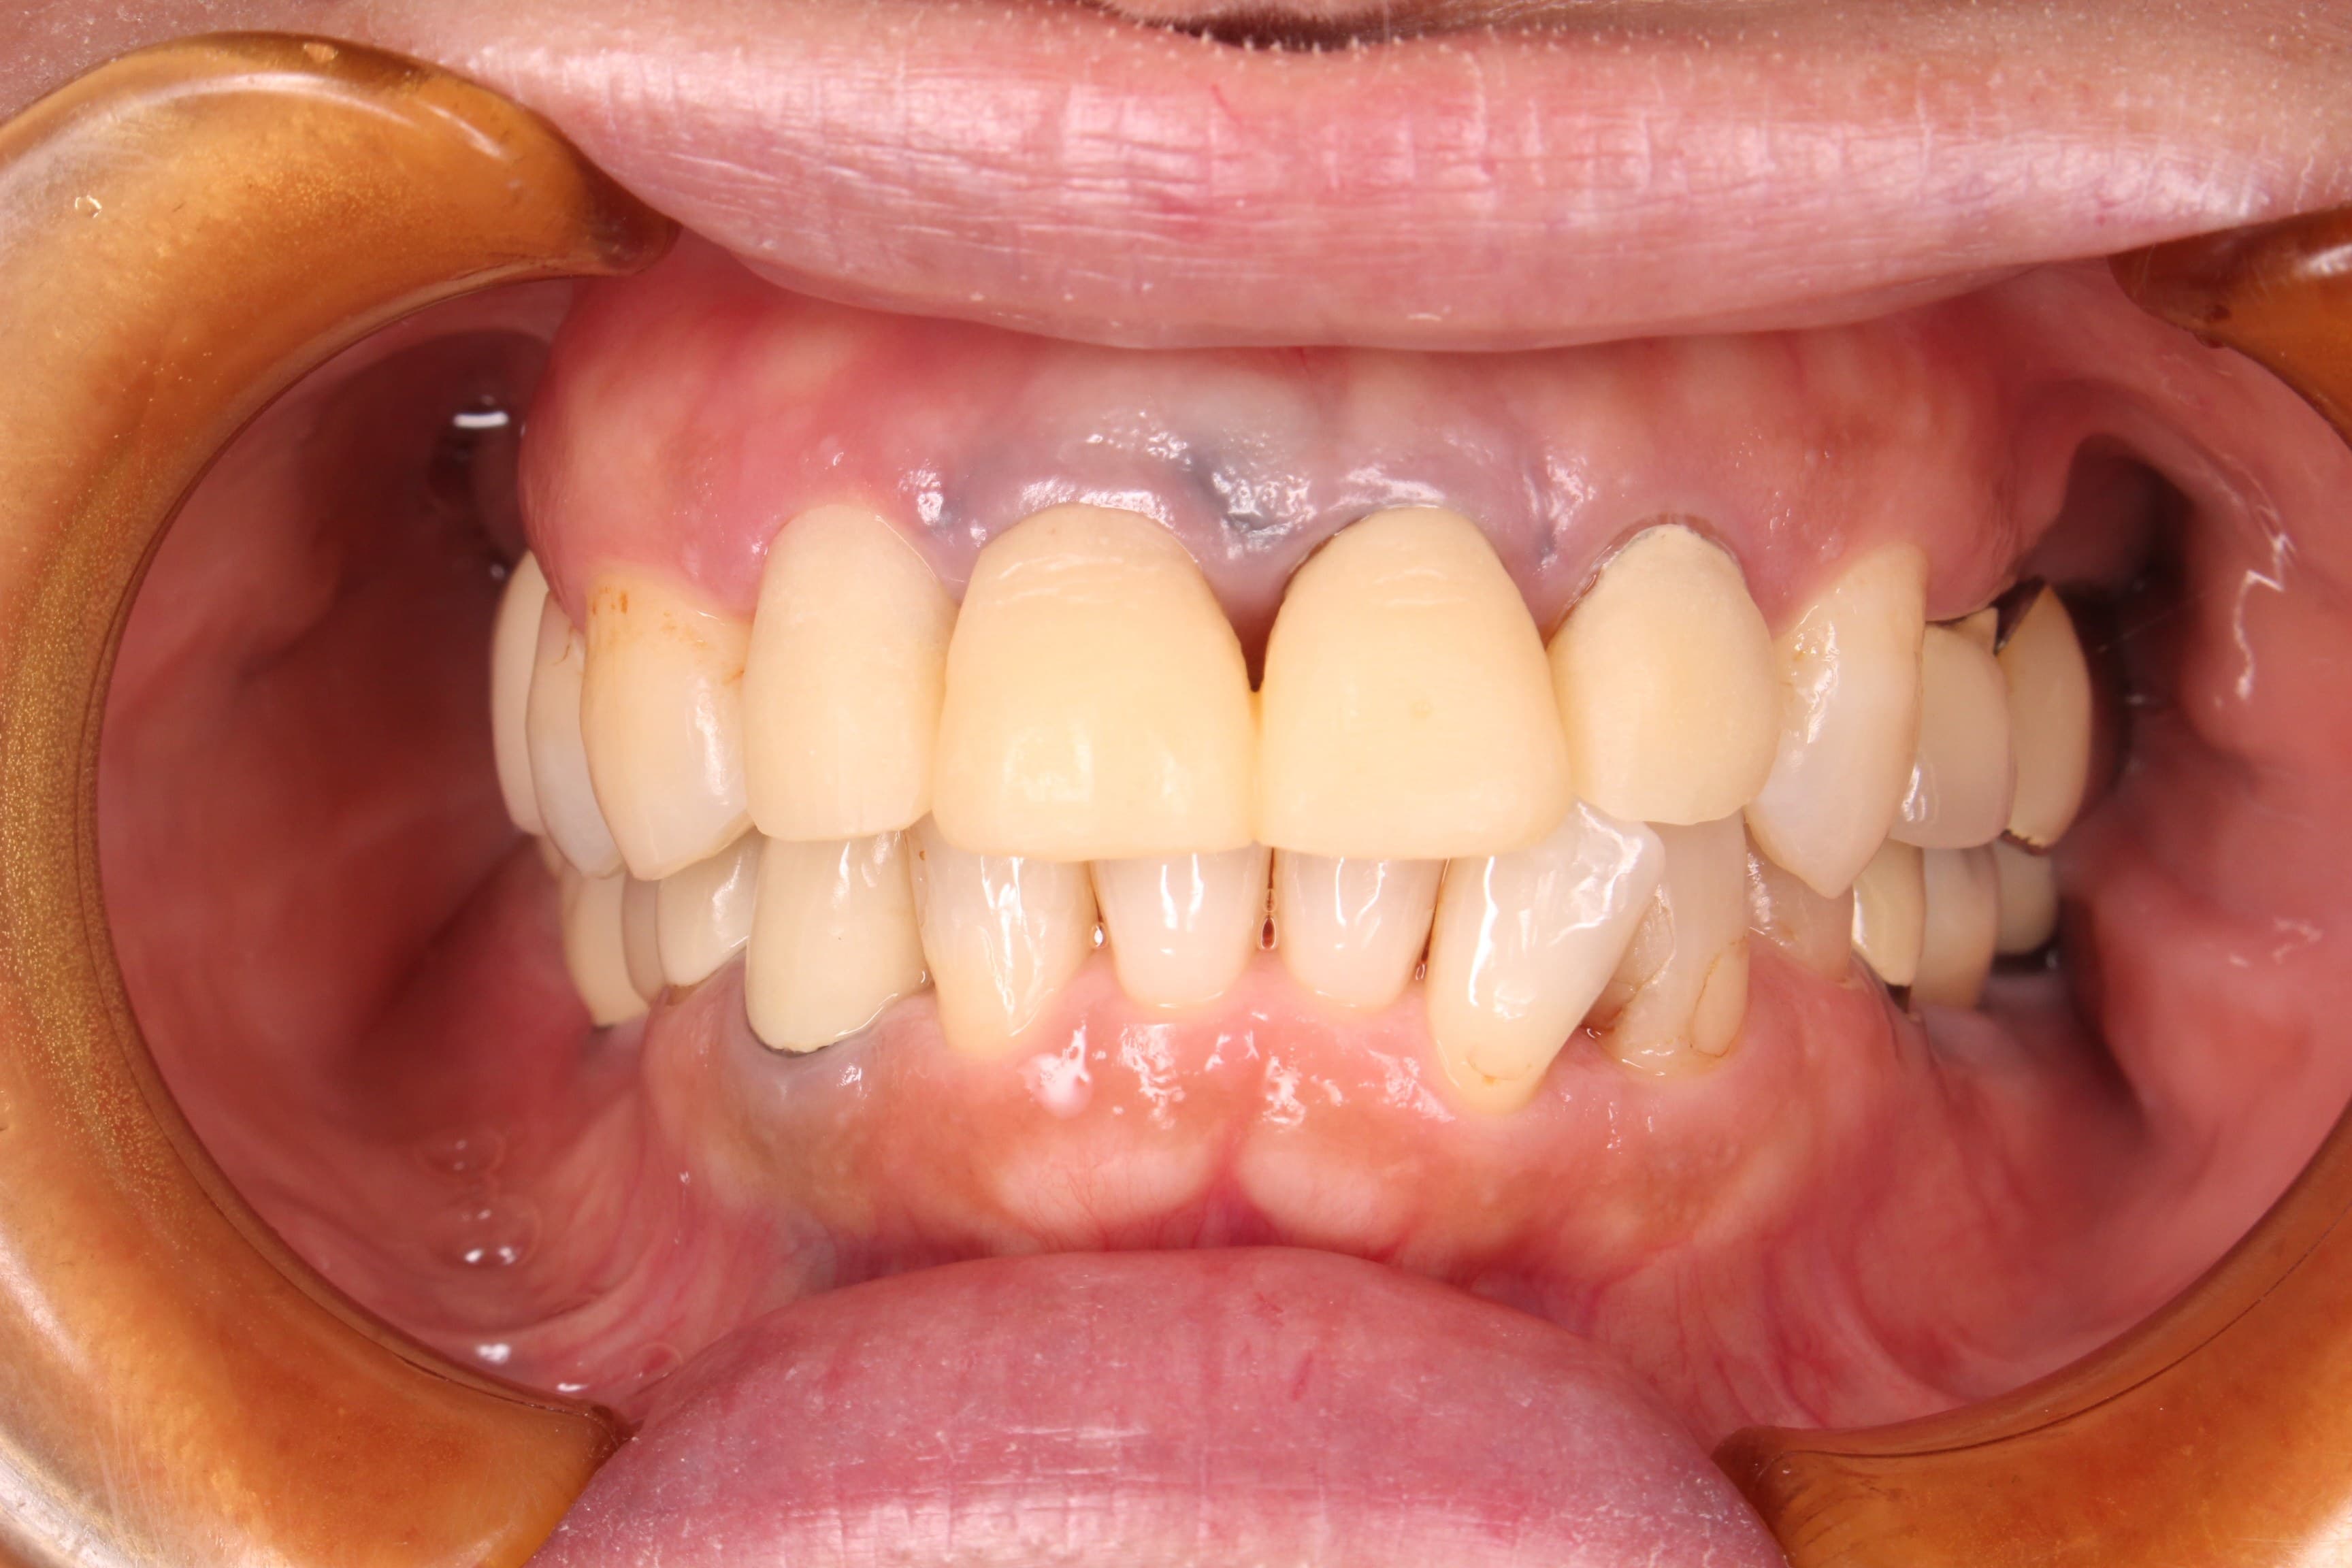

(歯周治療終了時の口腔内写真)

治療終了時には、以前までのご自身の口の状態が悪かった事を実感され、良くなったことについて非常に驚いていらっしゃいました。

現在、前歯は仮歯に置き換えて、歯の形態や歯肉の形態を作り込んでいます。また根の病気もあったので、専門根管治療をおこなっており、これらが終了したあと、セラミックの被せ物で審美的な補綴治療を行う予定です。